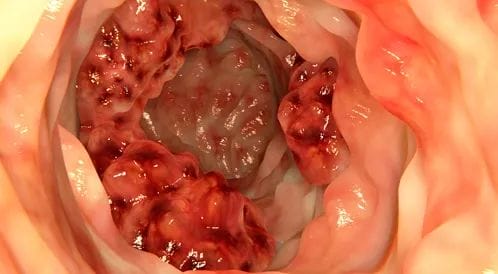

الفحص بمنظار القولون

يتميز الدكتور محمد كريم بالفحص بمنظار القولون حيث يمتلك خبرة تمتد إلى 27 عاما من الفحص بالمناظير، وفيه يستخدم منظارًا مرنًا يسمى منظار القولون لرؤية الجزء الداخلي من القولون والمستقيم، و في حالة ما وجد أورامًا حميدة في القولون، فسيقوم بإزالتها وإرسالها للفحص تحت المجهر للبحث عن الخلايا السرطانية.